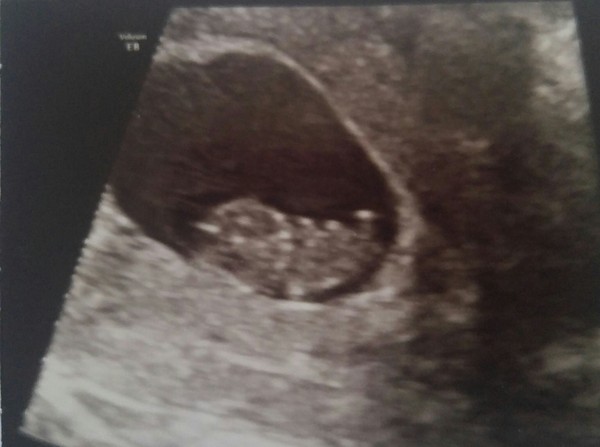

All ok, wriggling away. They have no idea what the blood was about.

So so relieved for you - It's just one worry after another but that scan photo is amazing.